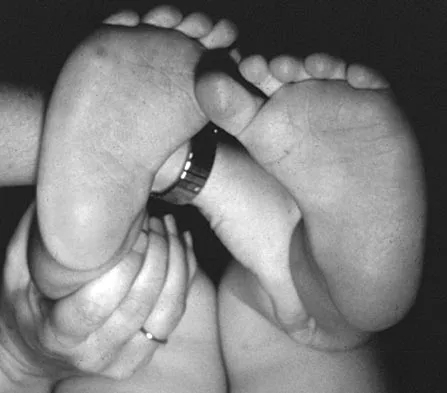

Question 50High Yield

Figure 6 shows the clinical photographs of a newborn who underwent a colostomy for an imperforate anus. Examination shows extended knees, flexed hips, and equinovarus feet. Dimpling is noted over the buttocks. Patients with these findings differ from patients with myelodysplasia in that they

Explanation